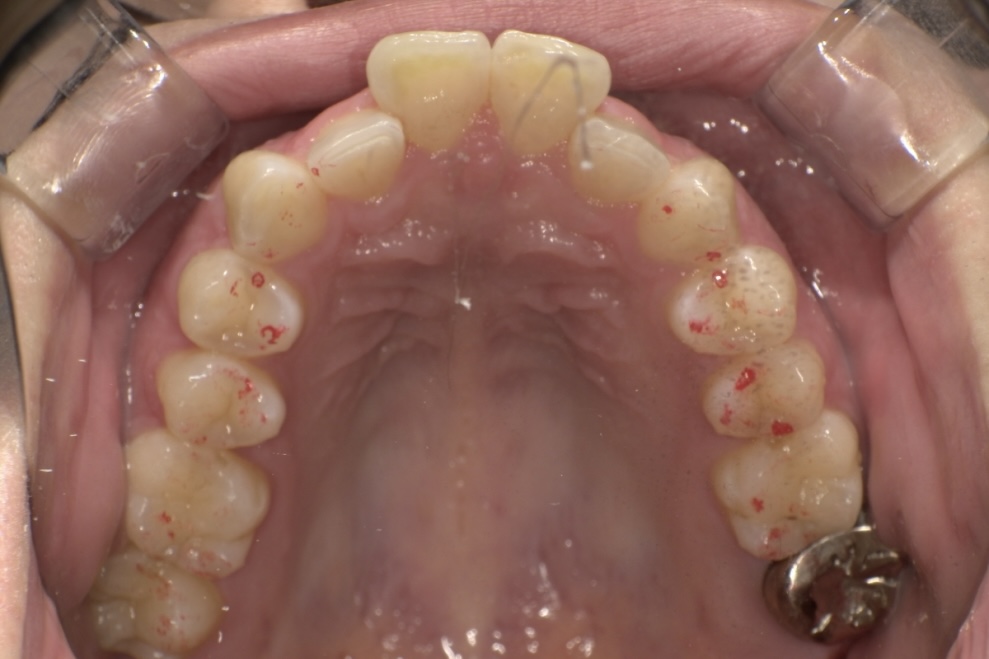

診断の結果、上顎前歯の唇側傾斜が強く、歯並びの状態だけを見ると抜歯を検討するケースでしたが、患者さまの「できるだけ抜歯は避けたい」というご希望を踏まえ、奥歯の遠心移動とIPR(歯と歯の間をわずかに調整する処置)を適切に組み合わせることで、抜歯を行わずに治療を進めました。

治療期間は1年10ヶ月、通院は2〜3ヶ月に1回と無理のないペースで進め、治療の経過を確認しながら計画的に歯並びと咬み合わせを整えました。

その結果、前歯の突出感や下の前歯のガタつきが改善し、前歯でしっかり噛める機能的な咬み合わせを獲得することができ、見た目と機能の両面で良好な結果が得られた症例です。

AFTER